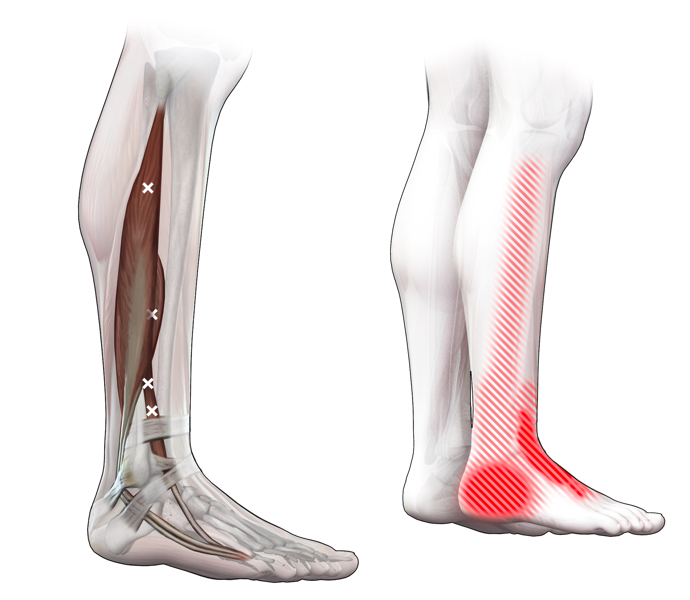

Spieren (Nederlands)

Spieren (nederlands)

Spieren (Latijn)

Spieren (latijn)

Trefwoorden

Trefwoorden